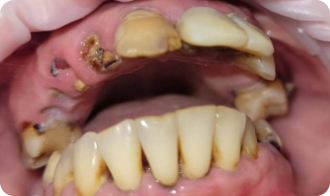

Установка All-on-4

До приёма:

• Полная адентия зубов

• Атрофия костной ткани

Результат:

• Установка имплантов Straumann

• Костная пластика

Срок: 2 дня